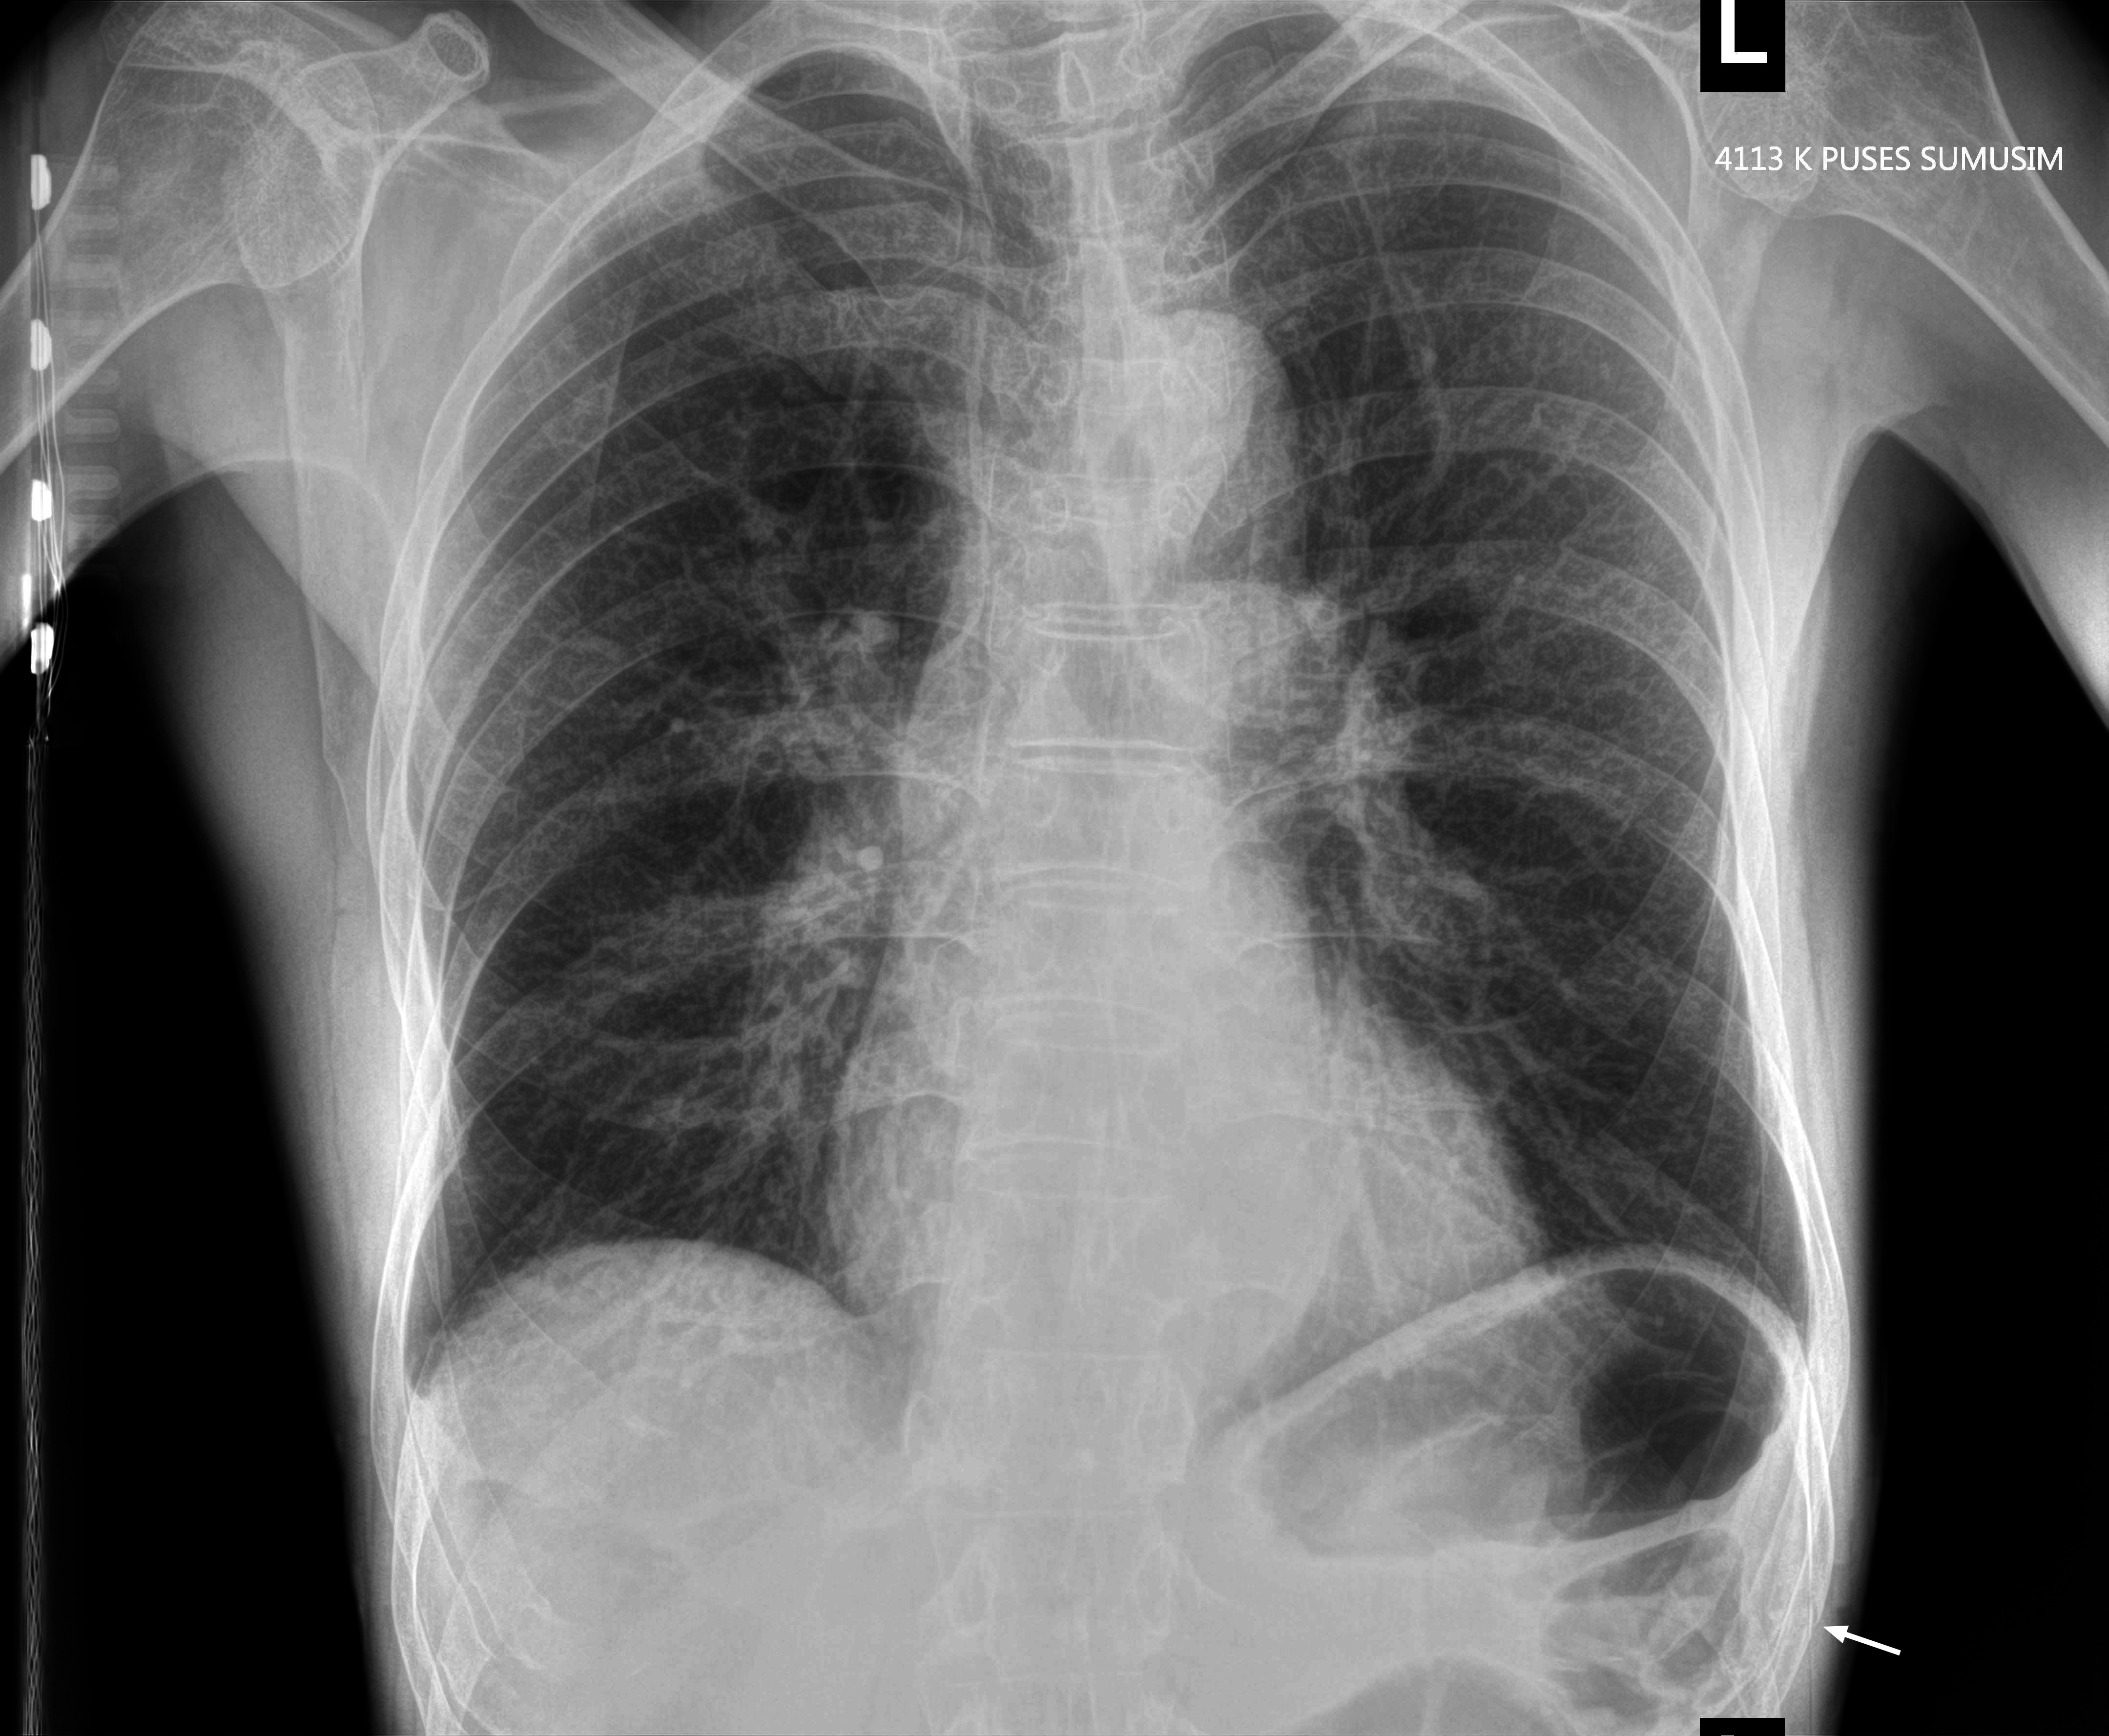

Мужчина средних лет, упал с лестницы 2 недели назад

Перелом ребра